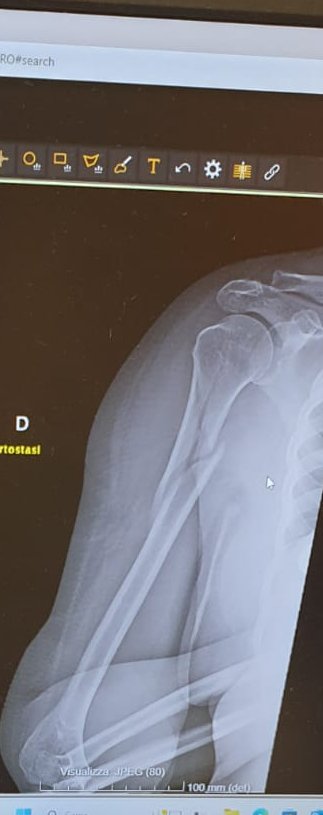

Il caso che ci segnala una lettrice pratese si distingue particolarmente, anche per un profano. Ricoverata la settimana scorsa dopo una caduta in strada, nei pressi di un cantiere mal segnalato, accusa un intenso dolore al braccio destro che non riesce più a muovere. In visita di emergenza-urgenza viene sottoposta a raggi X da cui emerge una frattura scomposta del collo dell'omero. Ma in reparto l'unico trattamento consigliato è l'applicazione del tutore e l'immobilizzazione delle dita.

La signora viene subito dimessa, ma non convinta. Il dolore è intenso e la preoccupazione alta. Così decide di farsi accompagnare da un'amica all'Ospedale universitario di Careggi, per un altro parere. E senza sorpresa nel più grande policlinico di Firenze, dopo la visita dispongono il suo ricovero per approntare un intervento chirurgico di riduzione della pericolosa frattura scomposta al braccio.